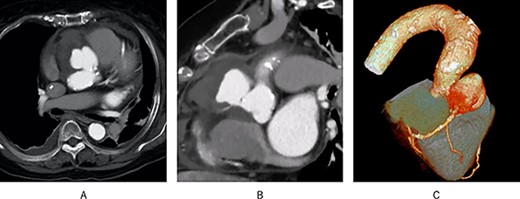

A 72-year-old woman with an elevated inflammatory response (white blood cell: 15 030/μl, C-reactive protein: 7.74 mg/dl) was transferred to our department for surgery of an aortic root pseudoaneurysm. Transthoracic echocardiography (TTE) revealed severe tricuspid regurgitation, moderate aortic stenosis (AS) and an aneurysm with a large ostium near the origin of the right coronary artery (RCA). Moreover, contrast-enhanced computed tomography (CT) revealed the RCA appeared to arise from the aneurysm (Fig. 1). The patient was scheduled to undergo elective surgery. However, on the third day of admission, creatine kinase MB increased from 2.6 to 23 U/l, urine volume decreased to about 10 ml/hour and 6 l of oxygen was required, so emergency surgery was performed.

Preoperative contrast-enhanced CT; (A) a pseudoaneurysm was found in the aortic root; (B) the RCA appeared to originate from the pseudoaneurysm; (C) 3D CT showed the same results.